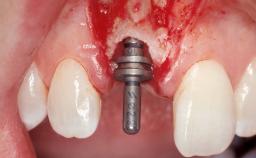

| # of Implants | 1 |

| Type of Implants | One-Piece |

| Attachment | One-Piece |

| Placement Protocol | Immediate implant placement |

| Bone Augmentation | Horizontal|Simultaneous |

| Augmentation Materials | Xenogenous|Membrane |